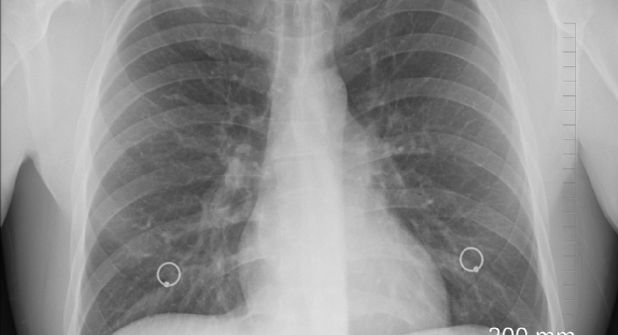

La medicina para tratar la fibrosis pulmonar idiopática (FPI)—una enfermedad pulmonar crónica e irreversible—fue rediseñada de manera más eficiente mediante la IA (Inteligencia Artificial) y probada en un paciente.

Durante la fase 2 del ensayo clínico, se evaluarán la seguridad, tolerabilidad, farmacocinética y eficacia preliminar de INS018_055 en pacientes con FPI, a los que se espera que este fármaco pueda ayudar en el tratamiento de esta enfermedad.